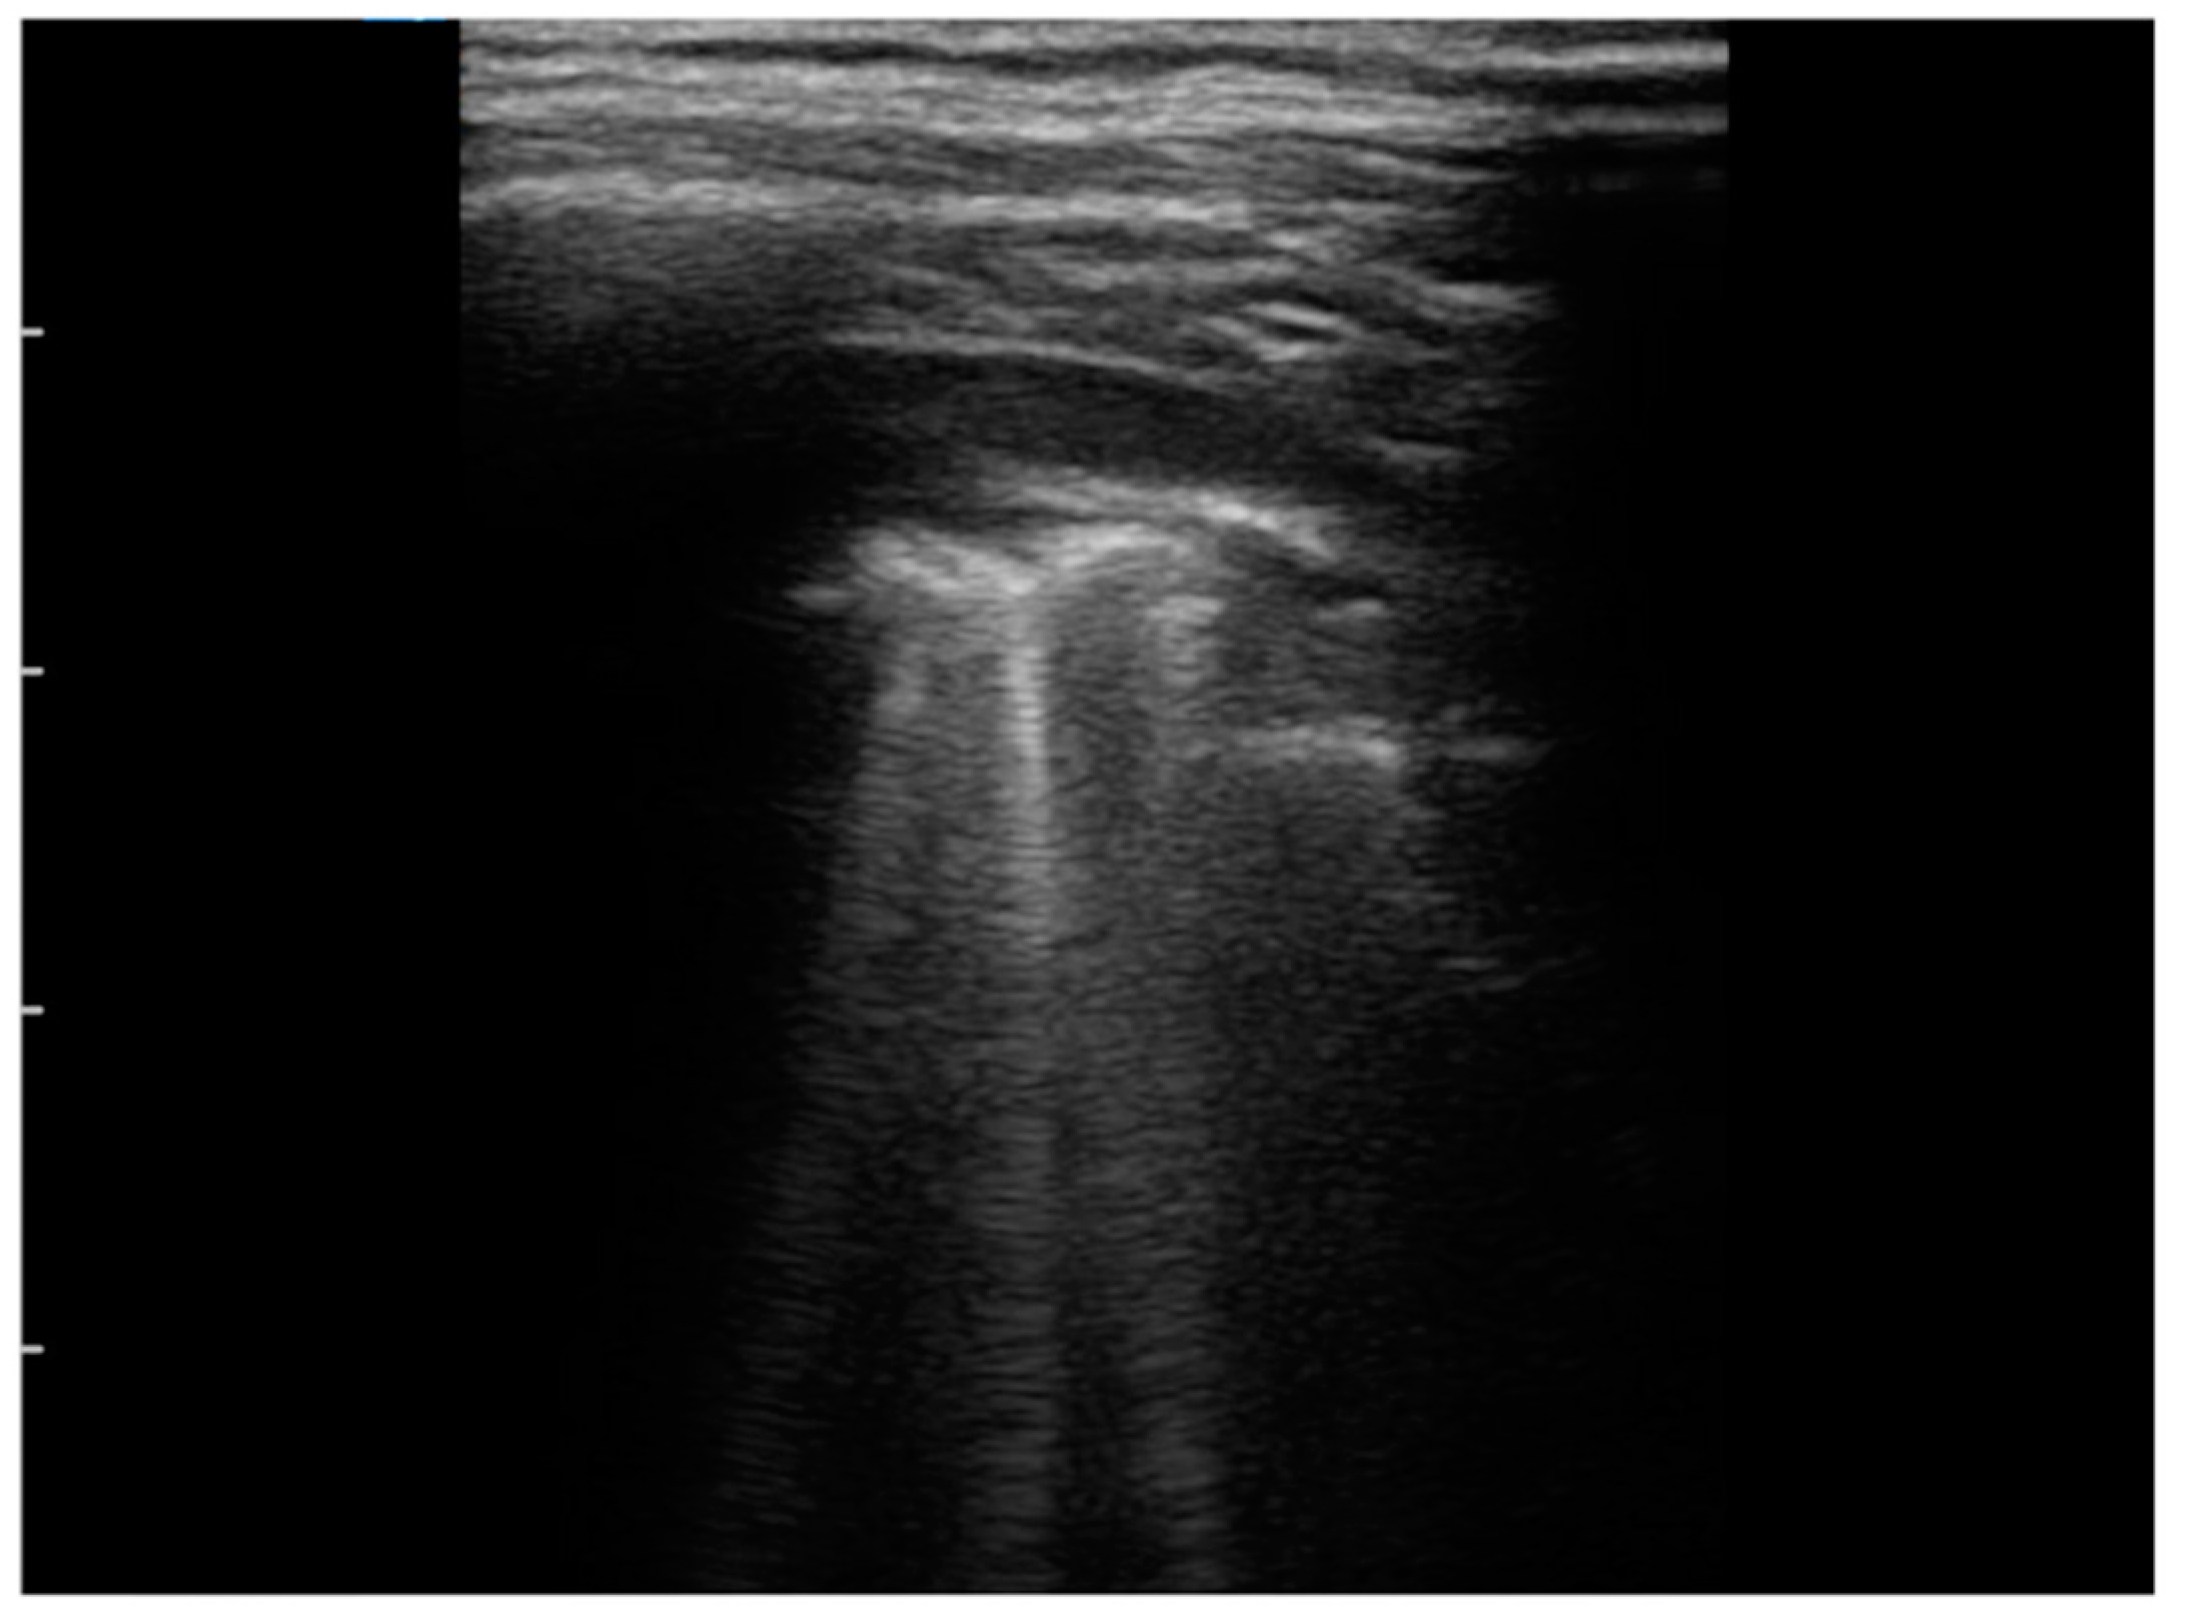

| Irregular/indented/broken pleural line, n (%) | 10 (100) | |

| B-lines, n (%) | 10 (100) | |

| Multiple/several B-lines, n (%) | 8 (80) | |

| White lung, n (%) | 5 (50) | |

| Sub-pleural consolidation, n (%) | 7 (70) | |

| Pleural effusion, n (%) | 9 (90) | |

| LUS score, mean ± SD | 10.5± 1.81 |